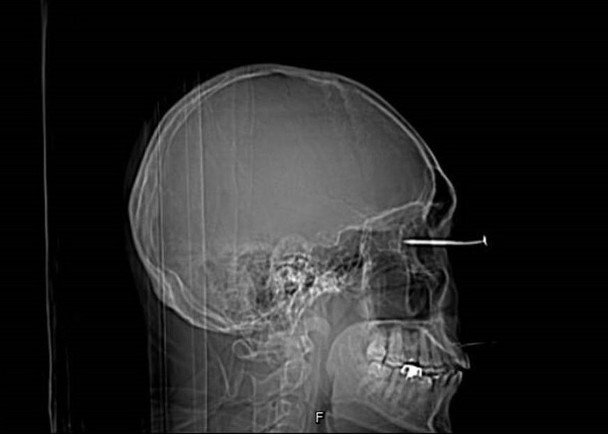

男子钉床板操作不慎 钉子反弹直插眼球

台湾媒体上周六(6日)报道,高雄市一名30多岁的男子近日在家平躺在地,使用钉枪钉床板时,因操作不慎,导致一支6公分长的钉子反弹并直插进他的右眼。

男子到医院就诊后,连医生亦不禁吓了一跳。尽管最后开刀手术顺利,但由于钉子贯穿眼球,伤及眼角膜、晶状体、玻璃体、视网膜、脉络膜及巩膜等多个部位,男子手术后视力严重受损,且难以复原。

医生表示,若民众遇到异物进入眼球,切勿擅自取出或以冲水等方式取出和排出异物,因眼球外有许多肌肉控制,而眼球上下左右转动时,均可能对眼球产生二次伤害。